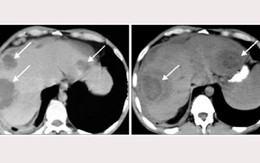

Những điều cần biết về ápxe gan

TT - Ápxe gan là tình trạng nhiễm trùng và gây ra ổ mủ bên trong gan, đây là một bệnh tương đối hiếm gặp. Nguyên nhân gây bệnh thường gặp nhất là ký sinh trùng và vi trùng hoặc do nhiễm nấm.